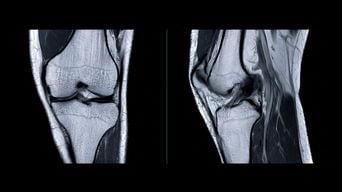

En principe, non. Pour réaliser une IRM du genou, on installe une antenne, qui est comme un manchon, autour du genou blessé. L’examen ne porte que sur le genou concerné, celui qui est douloureux. L’autre genou n’est pas visible.

Pour qu’une erreur se produise, il faudrait effectuer une exploration généralisée, ce qui n’est pas le cas lors d’une IRM du genou. Dans le cas où l’on recherche des lésions ligamentaires ou des atteintes des ménisques, une antenne spécifique est utilisée, centrée uniquement sur l’articulation à examiner.

Si l’examen avait concerné les deux genoux parce que le patient avait subi une blessure des deux côtés, on aurait réalisé une IRM sur un genou avec l’antenne dédiée, puis on aurait utilisé la même antenne sur l’autre genou. Ce sont deux examens distincts. L’imagerie pour rechercher des lésions des ligaments croisés, des ligaments collatéraux, des ménisques ou des fractures osseuses se fait avec des antennes spécifiques centrées sur chaque genou.

Les IRM modernes sont des appareils d’une grande performance. Elles permettent des coupes millimétriques, très précises, pour analyser toutes les structures et peuvent déceler les moindres contusions osseuses ou microdéchirures ligamentaires. Ce sont des examens d’une grande sensibilité, que les radiologues savent interpréter avec expertise.

Supposons qu’une IRM soit réalisée sur le mauvais genou. Lors de l’acquisition des images, on peut immédiatement identifier si c’est le côté droit ou gauche, car un genou droit n’a pas la même apparence qu’un genou gauche. Les appareils produisent des images avec un repère spatial, comme si le patient était devant le radiologue. Ainsi, si l’on indique à un radiologue de vérifier tel ou tel genou, il devrait s’en rendre compte si ce n’est pas le bon côté. Une telle confusion est quasiment impossible, surtout pour un patient comme Mbappé, où une équipe médicale complète se souviendrait de sa blessure.

Le radiologue aurait également pu être alerté par l’absence totale de lésions sur le genou qui était censé être blessé. Pour ces types de traumatismes, tous les ligaments croisés, antérieurs et postérieurs, ainsi que les ligaments collatéraux (médial et latéral), les ménisques, les os, et toutes les parties molles doivent être examinés pour déceler des dommages liés à la blessure. En général, pour une entorse au football, on s’attend à trouver au moins un léger épanchement, et à ressentir qu’il y a eu un traumatisme, même en l’absence de lésions ligamentaires. Un genou apparaissant totalement normal laisse perplexe. Le radiologue aurait donc été en droit de s’interroger. Ainsi, l’affaire Mbappé est assez singulière.